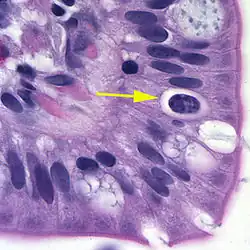

Oocyst in epithelial cyst of mammalian host

Isosporiasis, also known as cystoisosporiasis, is a human intestinal disease caused by the parasite Cystoisospora belli (previously known as Isospora belli). It is found worldwide, especially in tropical and subtropical areas. Infection often occurs in immuno-compromised individuals, notably AIDS patients, and outbreaks have been reported in institutionalized groups in the United States. The first documented case was in 1915. It is usually spread indirectly, normally through contaminated food or water (CDC.gov).[1]

The coccidian parasite Cystoisospora belli infects the epithelial cells of the small intestine, and is the least common of the three intestinal coccidia that infect humans (Toxoplasma, Cryptosporidium, and Cystoisospora).

At time of excretion, the immature oocyst usually contains one sporoblast (more rarely two). In further maturation after excretion, the sporoblast divides in two, so the oocyst now contains two sporoblasts. The sporoblasts secrete a cyst wall, thus becoming sporocysts; and the sporocysts divide twice to produce four sporozoites each. Infection occurs by ingestion of sporocyst-containing oocysts: the sporocysts excyst in the small intestine and release their sporozoites, which invade the epithelial cells and initiate schizogony. Upon rupture of the schizonts, the merozoites are released, invade new epithelial cells, and continue the cycle of asexual multiplication. Trophozoites develop into schizonts which contain multiple merozoites. After a minimum of one week, the sexual stage begins with the development of male and female gametocytes. Fertilization results in the development of oocysts that are excreted in the stool. Cystoisospora belli infects both humans and animals.

Microscopic demonstration of the large typically shaped oocysts is the basis for diagnosis. Because the oocysts may be passed in small amounts and intermittently, repeated stool examinations and concentration procedures are recommended. If stool examinations are negative, examination of duodenal specimens by biopsy or string test (Enterotest) may be needed. The oocysts can be visualized on wet mounts by microscopy with bright-field, differential interference contrast (DIC), and epifluorescence. They can also be stained by modified acid-fast stain.